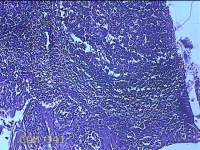

性别

女

年龄

7岁

鼻塞、咽异物感、打鼾、张口呼吸伴睡眠呼吸暂停2年。

双侧扁桃体

灰白粉红色扁桃体3.3x2.3x0.3cm两个,表面均有部分糜烂,切面灰白粉红色,结节状,质软。